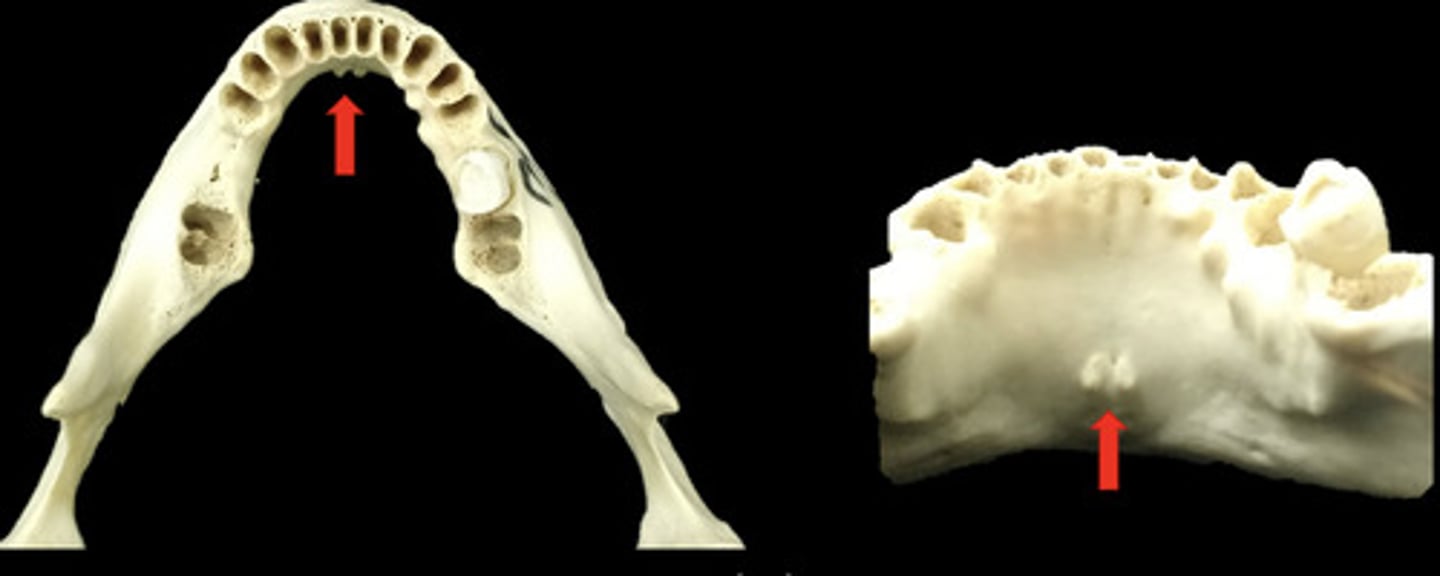

What is the mylohyoid ridge?

A linear prominence of bone located on the internal surface of the mandible

-serves as an attachment site for the mylohyoid muscle

-also referred to as inferior oblique ridge

What does the mylohyoid ridge look like radiographically?

information on mylohyoid ridge

dense radiopaque band that extends downward and forward from the third molar region at the level of the apices of the posterior teeth

What are nutrient canals?

anatomic structures of the alveolar bone through which neurovascular elements transit

Where are interdental nutrient canals most often seen?

in the anterior mandible, a region that typically has thin bone

information on nutrient canals

little lines of radiolucency found in maxillary & mandible

What do nutrient canals look like radiographically?